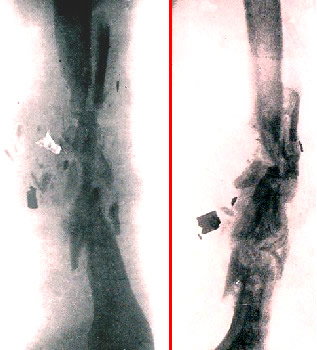

Two X-Rays of Fractured Arm With Metal Fragments,

From

the Journal of Roentgenology (1919)

but "shattered bones will be long a coming out, some at one dressing, and some at another; but when they are all out, and the rest clean and sound, then the bone will cover with good flesh"7.